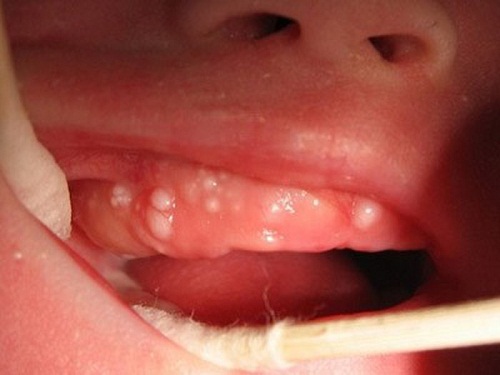

Theo PGS – TS Võ Trương Như Ngọc – Trưởng bộ môn Răng trẻ em – Viện Đào tạo Răng Hàm Mặt, phó giám đốc Trung tâm Kỹ thuật cao Răng hàm mặt Đại học Y (Hà Nội), trẻ sơ sinh mọc răng nanh sữa không phải là trường hợp hiếm gặp. Nanh sữa hay gặp ở trẻ sơ sinh từ 0 – 3 tháng tuổi, một số trường hợp gặp muộn hơn nhưng hiếm khi gặp trên 8 tháng tuổi, và nó xuất hiện ở hơn một nửa số trẻ mới sinh. Tuy nhiên tỷ lệ thực tế có thể còn cao hơn nữa do đây là một tổn thương lành tính, xuất hiện trong thời gian ngắn, ít khi gây đau đớn cho trẻ và thường tự vỡ rồi biến mất trong khoảng 2 tuần do vậy thường được bỏ qua không đến khám ở cơ sở y tế. Trường hợp nang to có thể tồn tại đến 5 tháng mà không gây biến chứng gì.

Chia sẻ về vấn đề này, BS Lê Huy Thành cho biết, không phải trường hợp nào trẻ mọc răng nanh cũng cần nhổ bỏ bởi mọi sự tác động đến cơ thể trẻ trong giai đoạn sơ sinh đều ít nhiều ảnh hưởng đến sức khỏe, tâm lý và sự phát triển sau này của trẻ. Tuy nhiên trong một số trường hợp đặc biệt, chúng ta nên nhổ bỏ những chiếc răng này cho trẻ càng sớm càng tốt để tránh hậu quả đáng tiếc.

Theo BS Thành, khi thấy trẻ có nanh mà ăn kém, quấy khóc, cần đưa bé đến nha khoa để được xử lý và nhổ răng nanh (nếu cần) một cách an toàn. Thủ thuật nhổ răng nanh cho trẻ sơ sinh tại nha khoa khá đơn giản, nhanh chóng. Đầu tiên trẻ sẽ được thăm khám để xem xét có cần nhổ răng không. Nếu việc nhổ răng nanh sữa là cần thiết, trẻ sẽ được vệ sinh răng miệng sạch sẽ, bôi thuốc gây tê giúp giảm đau trong quá trình thực hiện. Sau đó bác sĩ thực hiện bóc tách lớp vỏ răng nanh ra, các nhân màu trắng hoặc vàng nhạt tự vỡ ra ngoài sau đó không cần can thiệp thêm.